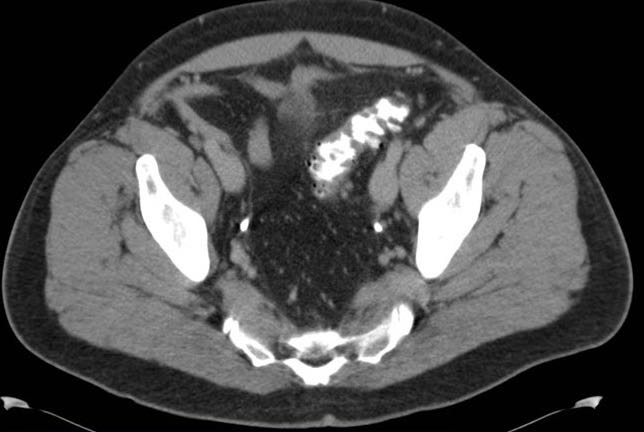

体格检查,体温升高到39.4℃,血压130/76mmHg,脉搏110次/分,呼吸20次/分,非急性窘迫,但有轻微的出汗。口咽清晰,有粘膜干燥。肺部听诊清音,心率正常,无杂音。 腹部检查显示左下象限中度压痛,有腹壁紧张。无反跳痛。无脊肋角压痛,未见腹股沟疝,生殖器检查结果均正常。直肠指诊,左侧直肠穹隆柔软,愈创木脂阴性。其余体检结果无异常。 血清实验室检测仅白细胞升高,为16×103/µL,其中中性粒细胞显著,尿检无异常。标准拍摄腹部平片,未见任何明显异常。后进行腹部和骨盆的CT